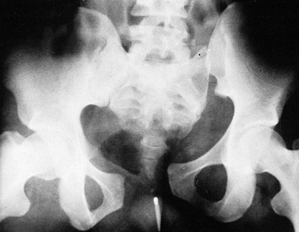

with others (Table 28.1), is most likely to occur following a very unstable, severely displaced, vertical shear fracture (Fig. 28.1). Fractures caused by lateral compression can also lead to posterior complex pain, however.

Figure 28.1. Very unstable vertical shear fracture of the pelvis.